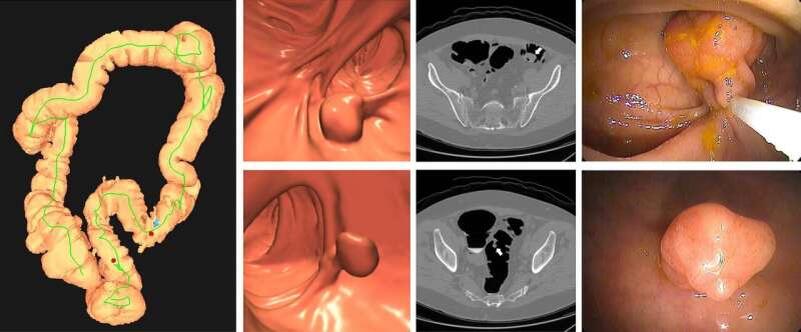

Согласно новому исследованию, опубликованному в журнале «Radiology», КТ-колонография (виртуальная колоноскопия) оказалась более эффективной и экономически выгодной для скрининга колоректального рака по сравнению с анализом ДНК кала (mt-sDNA).

Колоректальный рак — вторая по частоте причина смерти от онкологических заболеваний в мире. Раннее выявление предраковых полипов позволяет предотвратить развитие опухоли и снизить затраты на лечение.

• КТ-колонография — визуализация толстой кишки с помощью компьютерной томографии.

• Анализ ДНК кала (mt-sDNA) — выявление биомаркеров рака в образцах стула.

• КТ-колонография снижала риск развития рака на 70–75%.

• Анализ ДНК кала — только на 59%.

• КТ-колонография не только эффективнее, но и дешевле в долгосрочной перспективе.

• КТ-колонография каждые 3 года для небольших полипов (6–9 мм).

• Колоноскопия — только при обнаружении крупных образований (≥10 мм).

«КТ-колонография не только лучше выявляет рак, но и экономит средства. Кроме того, она позволяет оценить состояние других органов — например, выявить остеопороз или сердечно-сосудистые заболевания.»

Хотя колоноскопия остается «золотым стандартом» диагностики, КТ-колонографияболее безопасный, доступный и экономичный метод для массового скрининга.

Анализ ДНК кала также эффективен, но уступает по точности. Оптимальным решением может стать гибридный подход, сочетающий оба метода.